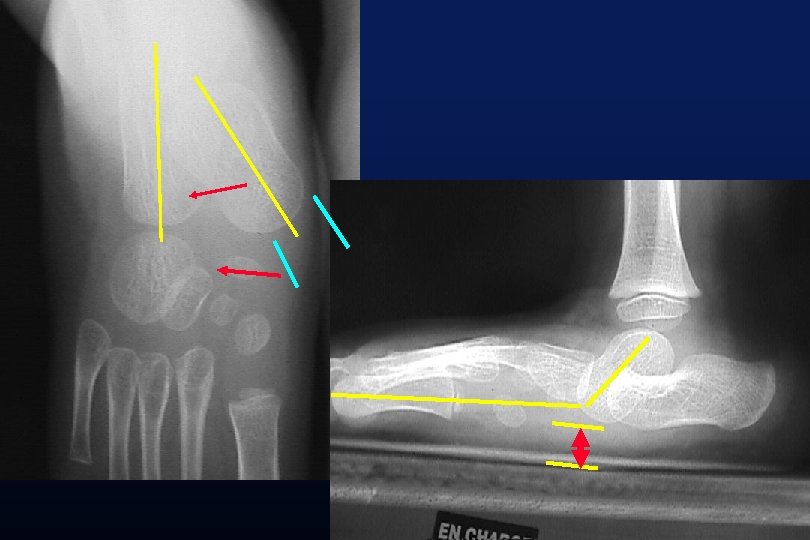

DEFINITION DIMINUTION DE LA HAUTEUR NAVICULAIRE

DEFINITION AUGMENTATION DE LA DIVERGENCE TALO CALCANEENNE VALGUS DU CALCANEUM

TRANSLATION MEDIALE ABAISSEMENT DE LA GROSSE TUBEROSITE DU CALCANEUS

Evans